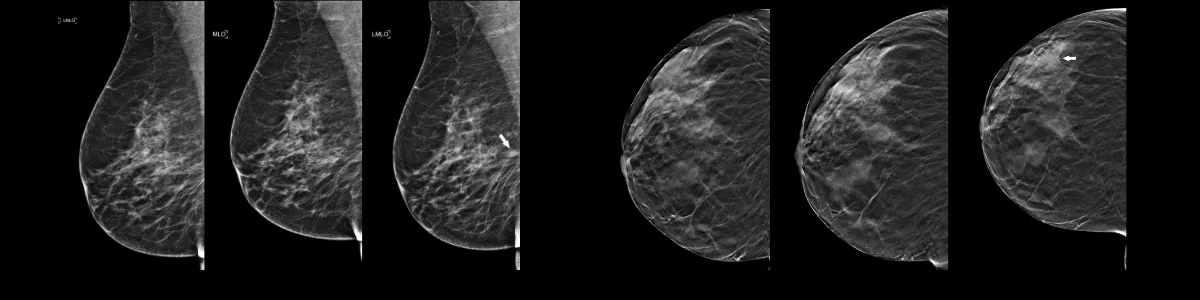

The VBCSS contributes to collaborative national studies of breast cancer screening and diagnosis that focus on evaluating real-world performance of breast cancer screening and diagnosis. We are a founding member of the Breast Cancer Surveillance Consortium (BCSC) and collaborate frequently with the Cancer Intervention and Simulation Modeling Network (CISNET). Through both consortia we engage in active research covering a wide variety of topics in breast cancer screening, diagnosis, treatment, and survivorship.

The VBCSS provides a framework for quality improvement initiatives and research on breast cancer screening and diagnosis. We provide quality assurance services to the participating facilities to support quality improvement initiatives and ensure compliance with FDA and American College of Radiology requirements for mammography facilities.